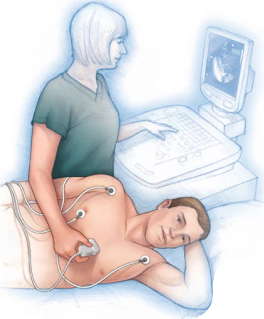

Get a detailed heart ultrasound to check structure and function. You will receive clear images and professional support. This service helps accurate cardiac assessment.